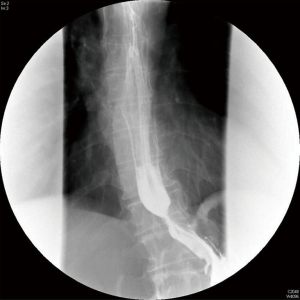

Upper gastrointestinal tract endoscopy disclosed a giant submucosal mass with a smooth surface that was located 18 to 40 cm from the incisors. Multiple biopsy specimens revealed inflamed mucosa with hyperaemia. There was no evidence of malignancy. Ultrasonic gastroscopy disclosed a giant protrusion of the esophagus located 18 cm from the incisors that originated from the submucous and was suspected to be a neurofibroma because of its homogeneous and hypoechoic lesion with clear margins. Distal esophagus and gastroesophageal junction was normal (Figures 1,2). A barium swallow showed a large intraluminal mass of the upper esophagus and compensatory dilatation of the proximal esophagus. A slightly irregular mucosal surface indicated a probable benign esophageal tumor (Figure 3). The patient underwent cervical, cardiac and abdominal ultrasound, which were unremarkable. Blood counts, biochemistry values and tumor markers levels were all found to be within normal limits.